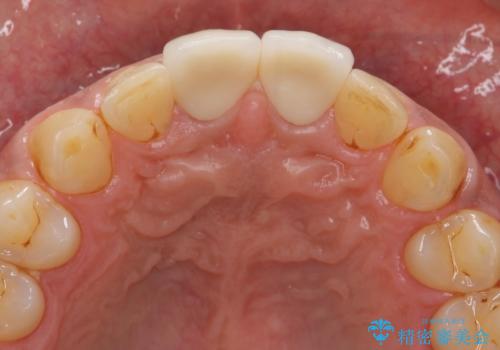

歯ぐきからの出血 膿が出る 前歯根管・セラミック治療

- 体調により前歯部の歯ぐきから出血や膿が出ることの改善を求めて来院されました。

X線写真より、根尖部に透過像が認められ根管治療・ファイバーコア築盛・セラミッククラウンの作製が必要な状態です。

- 46万円(仮歯・根管治療・ファイバーコア・ジルコニアクラウン×2)費用は治療当時の料金となります